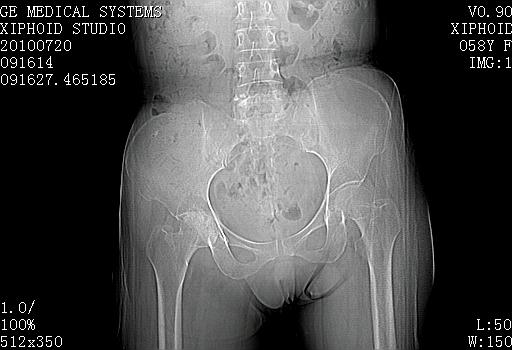

58岁女性,右髋不适,跛行月余。

先天髋关节发育不良,右侧关节囊积液

右侧股骨头缺血、坏死合并双侧关节腔积液。

髋关节类风湿性关节炎。关节间隙狭窄如细线状,股骨头和髋关节面均有多数小囊状凹陷,髋臼边缘唇样增生为继发退行性改变。

患者有明确类风湿关节炎病史,明确见其环指畸形尺侧偏。本例不象缺血性坏死,我努力往类风湿性关节炎靠,可是没发现典型病例可参考。

关节肿胀明显,关节间隙明显变窄,但骨质增生不多,是要考虑类风关,需与结核及骨性关节炎鉴别,髋臼前柱的囊变边缘光整,符合邻关节骨囊肿表现,但股骨头内囊肿边缘毛糙,应该是病变侵蚀所致,需进一步完善病史及相关检查鉴别

滑膜增生,关节腔积液,髂腰肌囊扩张,关节面软骨侵蚀破坏,间隙狭窄,股骨头变形,老年女性,有明确ra病史,符合ra关节炎,合并退变。

考虑右侧髋关节类风湿性关节炎并关节积液。

考虑右侧髋关节类风湿性关节炎并关节积液

滑膜增生,关节腔积液,髂腰肌囊扩张,关节面软骨侵蚀破坏,间隙狭窄,股骨头囊变,老年女性,有明确ra病史,符合ra关节炎,合并退变。支持!

结合病史符合类风湿性关节炎改变

髋关节类风湿性关节炎。